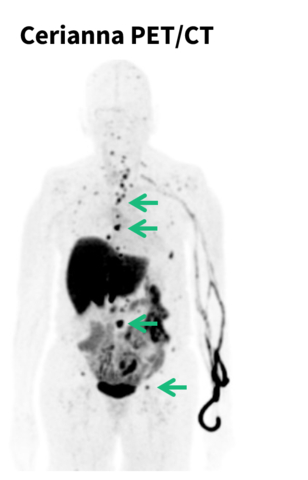

- GE HealthCare’s Cerianna (fluoroestradiol F18) injection is the first and only U.S. Food and Drug Administration (FDA) approved imaging agent to help clinicians assess estrogen receptor positive (ER+) lesion status in recurrent or metastatic breast cancer.

ARLINGTON HEIGHTS, Ill.--(BUSINESS WIRE)--GE HealthCare (Nasdaq: GEHC) today announced that the NCCN Clinical Practice Guidelines in Oncology (NCCN Guidelines®) for clinicians now recommend considering fluoroestradiol (FES) positron emission tomography (PET) for systemic staging in patients with recurrent or metastatic lobular breast cancer. GE HealthCare’s Cerianna™ (fluoroestradiol F18) injection, available in the United States, is the only FDA-approved imaging agent for the detection of estrogen receptor positive (ER+) breast cancer metastases, including lobular breast cancer. The updated NCCN Guidelines® expand the recommendation for the use of FES PET imaging in ER+ disease. In 2023, FES PET was included in the NCCN Guidelines for systemic staging of recurrent/stage IV ER+ breast cancer.

Cerianna is a molecular imaging agent indicated for use with PET imaging for the detection of ER+ lesions as an adjunct to biopsy in patients with known or suspected recurrent or metastatic breast cancer. Cerianna works by binding to functional ER lesions and then the whole body is imaged by PET scan to help doctors assess and treat lobular breast cancer appropriately. With its diffuse growth patterns, detection and biopsy of ILC can be more difficult. Cerianna provides an alternative method to assess ER status across the whole body.